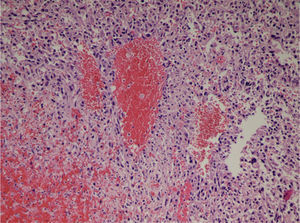

The patient came to our Emergency Department 48h after the MRI test due to epigastric pain and syncope. She presented with tachycardia (HR 130), hypotension (70/40) and tachypnea (RR 40). The blood work-up showed anemia (Hb 5.8), severe thrombocytopenia (platelets 42,000) and altered coagulation (INR 2.1). The patient was hemodynamically stabilized with fluid therapy and the transfusion of 6 units of packed red blood cells; the coagulation was corrected with the transfusion of 4 pools of platelets and 2000ml of fresh plasma. At that time, we assessed the magnetic resonance (Fig. 1), which demonstrated the existence of a voluminous liver mass measuring 18cm×12cm in the right liver lobe with intralesional bleeding.

The patient was assessed by the Interventional Radiology Department of our hospital. Abdominal ultrasound showed that there was no intra-abdominal free fluid. At this time, the possibility of performing arteriography and embolization of the right hepatic artery was ruled out due to that fact that the intratumoral bleeding was from the right portal branch. The patient was taken to surgery, where we carried out an extended right subcostal laparotomy and observed a large tumor mass that occupied the entire right liver lobe from the right dome of the diaphragm to the pelvis, which was elastic in consistency and violet in color (Fig. 2). We performed right hepatectomy under total vascular exclusion. The patient was discharged on the 8th day post-surgery with no complications. In the pathology study of the surgical specimen, a neoplastic proliferation of epithelioid or fusiform cells was observed with atypia that formed nests or vascular structures interspersed with areas of hemorrhage and necrosis, showing cellular uptake with vascular markers (CD31, CD34, F.VIII), compatible with high-grade angiosarcoma (Fig. 3).

The microscopic study of the surgical specimen reveals a neoplastic proliferation of epithelioid cells with atypia forming nests or vascular structures interspersed with areas of hemorrhage and necrosis, showing cellular uptake with vascular markers (CD31, CD34, F.VIII), compatible with high-grade angiosarcoma.